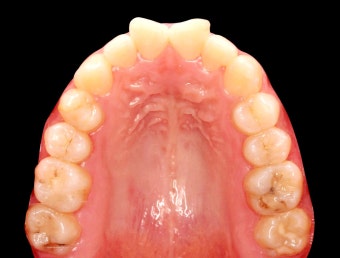

2. 정기 검진과 관리가 꼭 필요한 이유

- 임플란트·틀니는 3~6개월마다 정기 검진 필수. 초기 3개월은 적응 기간.

- 자연 치아 vs 임플란트: 자연 치아는 완충 역할을 하는 치주 인대가 있으나, 임플란트는 없어 합병증 발생 위험↑.

- 합병증(나사 풀림, 파절 등)은 초기 자각 어려움 → 정기 검진 필수.

- 조기 검진은 작은 문제도 빠르게 발견 → 큰 문제 예방 가능.

- 최소 6개월마다 구강 검진 권장 → 큰 증상 없어도 예방 차원 중요.